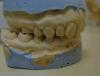

ИМХО №1:

1. Удаление 2.2

2. ортодонтическое "подтягивание" 2.4, 2.5, 2.6, 2.7

3. протезирование 2.3, 2.4, имитируя коронками соответственно зубы 2.2 и 2.3

ИМХО №2:

2. ортодонтическое устранение скученности 1.2, 1.1, 2.1, 2.3

Боюсь, что впихнуть (даже если удастся его вылечить) 2.2 на место 2.3 не получится- мало там для него места, да и фронт уже в тесноте. Хотя, я не ортодонт далеко, запросто могу много не понимать.

Насчет моста 2.3-2.4, то там, опять же, между ними места почти нет, получится не красиво (а, в общем-то, за этим и гонимся), а дистальный сдвиг зубов (2.4, 2.5, 2.6, 2.7) для получения этого места, как мне помнится, более труден, чем сдвиг вперед.